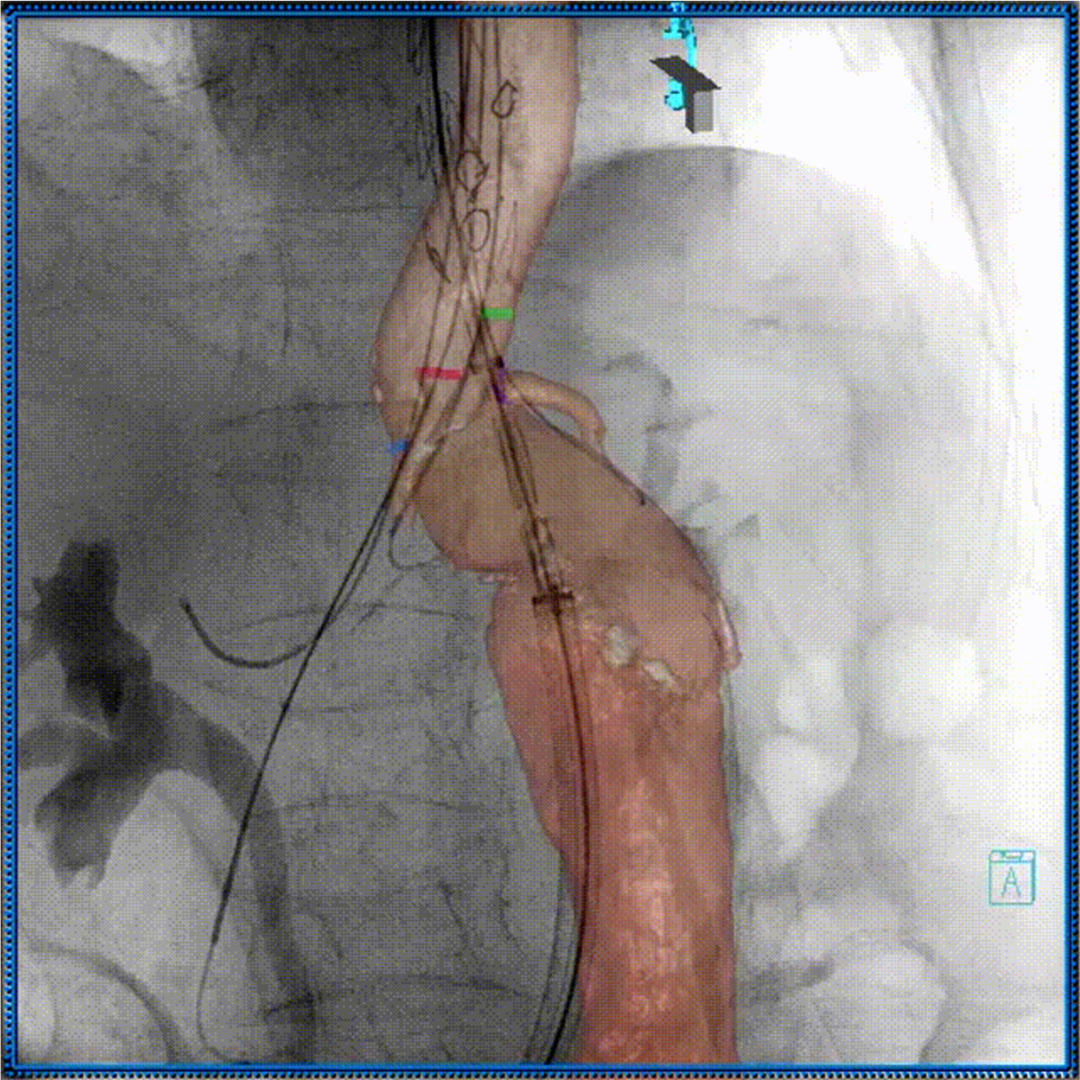

3D影像引导下完成窗口超选、置管及确认

肠系膜上动脉重建

左肾动脉重建

右肾动脉重建

四分支重建后造影,各分支血流通畅